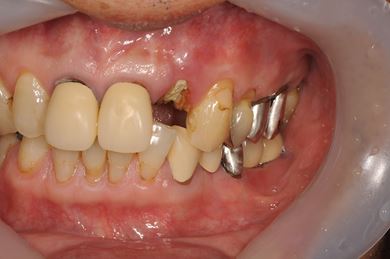

| 性別/年齢 | 男性 / 61歳 | ||||||||||||||||||||||||||||||||

| 主訴 | 奥歯のインプラント治療を希望。 | ||||||||||||||||||||||||||||||||

| 治療方針 | インプラント治療にて、機能的・審美的回復を行う。 | ||||||||||||||||||||||||||||||||

| 治療内容 | インプラント4本、メタルボンドセラミッククラウン4本 | ||||||||||||||||||||||||||||||||

| 総治療費 | 1,508,220円 | ||||||||||||||||||||||||||||||||

| 治療期間 | 7ヶ月 |